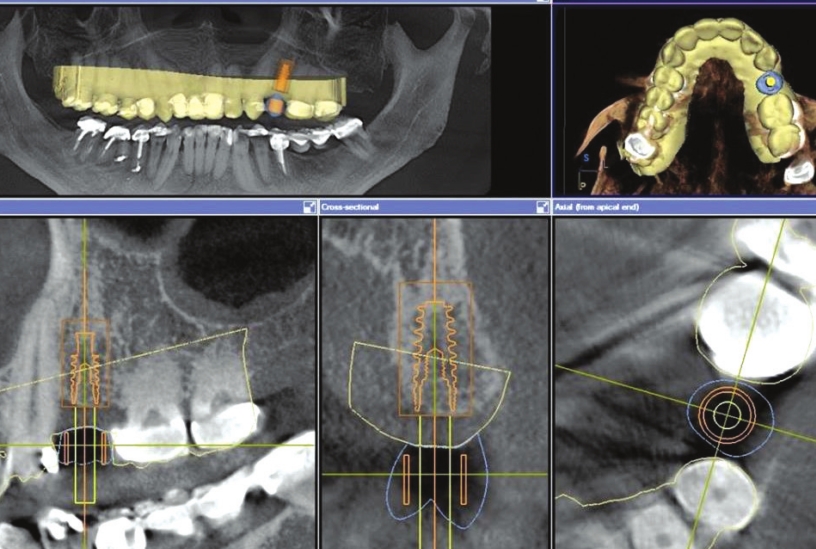

Step 3:

Then the two scans are stitched together (virtually overlapped) to plan a dental implant in the ideal position to support the future tooth already designed. By stitching both images, one can see where the details of the future crown lie and planning of the implant position is able to be done confidently. This “perfect placement” assures we have the proper loading forces (compression from chewing) on our future crown for the implant and supporting bone structure. Here, we can also determine if an extra bone augmentation procedure is necessary.